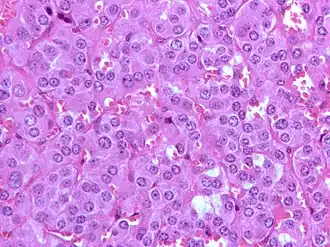

Een feochromocytoom is een zeldzame tumor van de chromaffiene cellen in het bijniermerg (90%) of chromaffiene cellen elders in het lichaam (10%). Indien de tumor gesitueerd is in het bijniermerg, is dat in 95% unilateraal, in 5% echter bilateraal. Het is een van de twee hoofdvormen van paragangliomen.